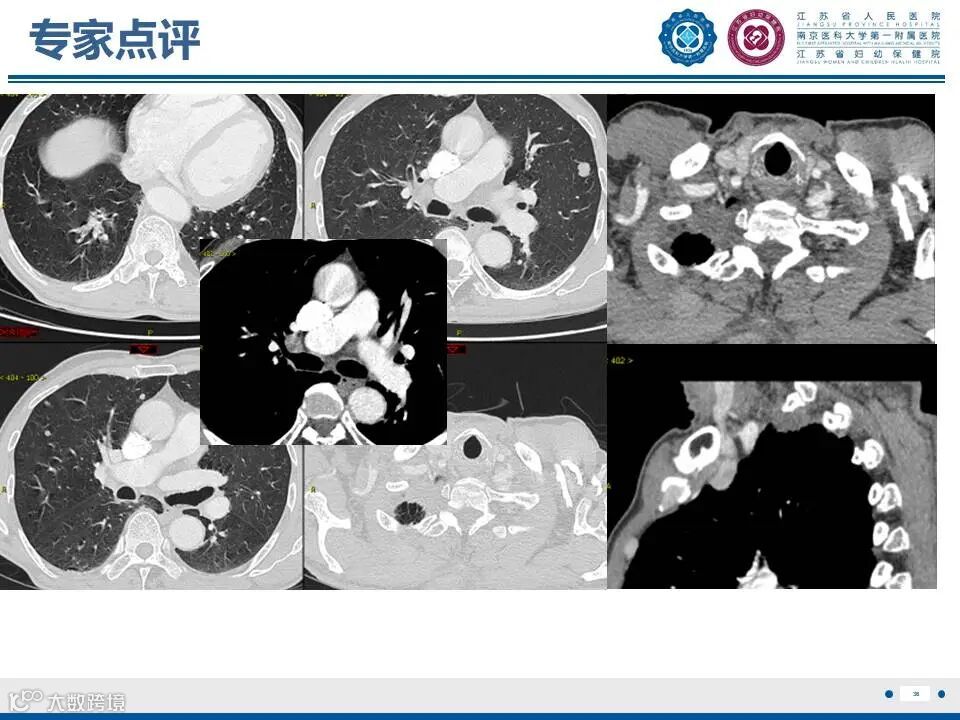

肺上沟瘤

——肩痛背后的致命危机